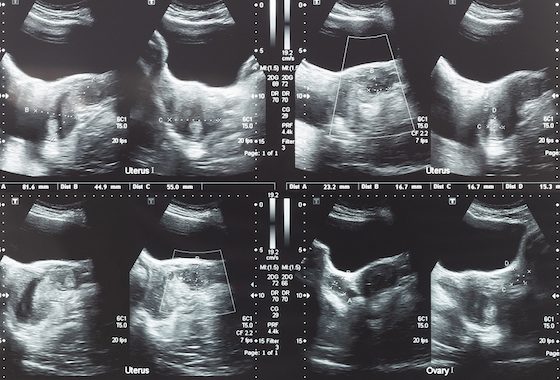

Miomat janë në shumicën dërrmuese tumore beninje (pra jo kanceroze). Shumë rrallë (1/1000 apo 1/10000), ato mund të shndërrohen në kancer dhe në këto raste ato quhen leiomiosarkoma.

Miomat nuk rrisin rrezikun për kancer në endometër, ovare apo në qafën e mitrës. Femrat shtatzëna të cilat njëkohësisht kanë edhe mioma mund të kenë probleme gjatë shtatzënisë apo lindjes. Ndër komplikacionet më të mundshme përmendim:

Lindje me operacion cezarian është gjashtë herë më e shpeshtë në rastin kur shtatzëna ka edhe mioma.

Paraqitje pelvike ose podalike e bebit (bebi nuk është i paraqitur mirë për lindjen natyrale). Mungesë të progresionit të lindjes.

Distako apo shkolitje të placentës – placenta shkëputet nga muri i mitrës përpara lindjes. Kur kjo ndodh bebi rrezikohet nga asfiksia ndërkohë që nëna rrezikon nga hemorragjia retro-placentare.

Lindje para kohe e bebit. Megjithatë shumica e pacienteve që kanë mioma nuk përjetojnë ndonjë nga komplikacionet e sipërmendura.